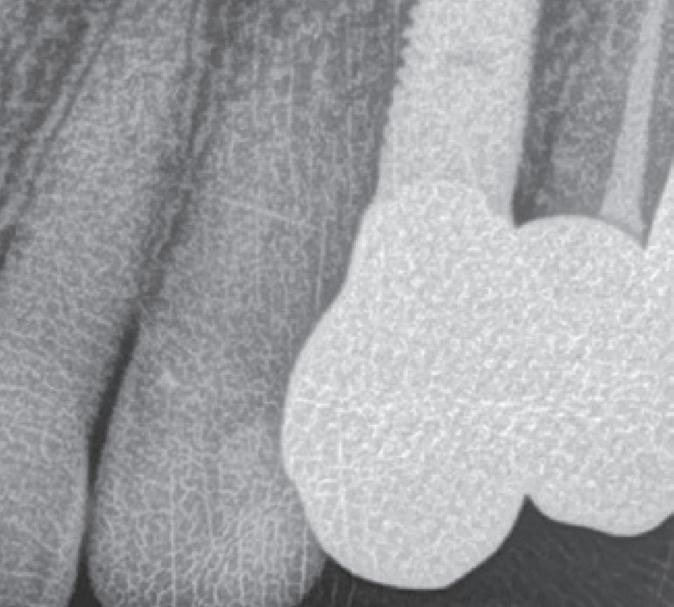

In 1975, one of my patients who was 18 years old became involved in a car accident; he hit the steering wheel with his chin and sustained 2 horizontal fractures in his 31, both quite a way subgingivally. The 41 and 32 were intact. The normal treatment at that time would have required extraction of the 31 and the placement of a partial denture or a bridge to replace the missing tooth.

Knowing that he had nothing to lose, he agreed to let me experiment on him. I extirpated the 31, drilled 10mm past the apex using a sterile Kurer Post spiral drill that matched the diameter of my titanium wire. I sterilised the Titanium using a

Yes, I did stick my neck out, but the result ended being a lot better for the patient than if we had opted for a bridge or a partial denture. The biological cost was negligible and we bought him 30 years of function until a better and more modern treatment became available.

In the current regulatory environment, treatment such as I described is not only illegal and would result in crippling fines being imposed by the TGA, but possibly result in losing one’s right to practice. If I had made a conventional bridge, the teeth either side would have been compromised and possibly lost by now, a partial denture would have caused periodontal problems.